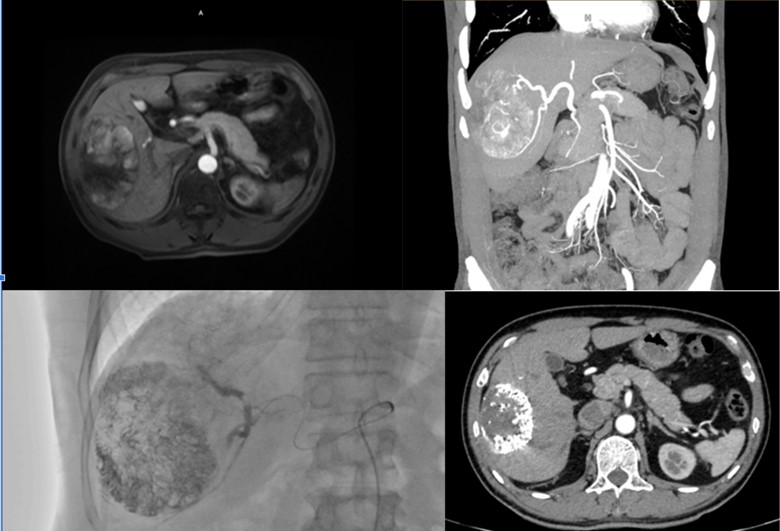

Hình ảnh 2: Khối ung thư biểu mô tế bào gan kích thước 7x11cm, có nhánh mạch nuôi u rõ. Bệnh nhân được nút mạch hoá chất (TACE) tại BVUBHN. Trong quá trình can thiệp u lắng đọng hoá chất tốt, nhánh mạch nuôi u được nút tắc hoàn toàn. Phim chụp kiểm tra sau điều trị cho thấy u hoại tử hoàn toàn, không còn phần tăng sinh mạch và ngấm thuốc